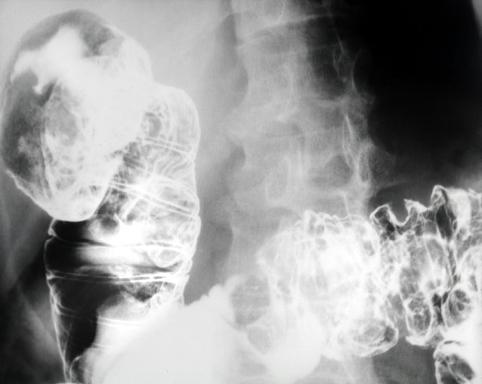

소장을 중심으로 다발융기를 주체로 한 악성 림프종---1970년대의 증례

[Image-ID:5499]

악성 림프계종양/악성 림프종

십이지장/2개 이상

검사방법

X-P

종양의 최대경(밀리미터)

25~29

다발종양(동일 장기)

유(동시성)

다중종양(다수의 장기)